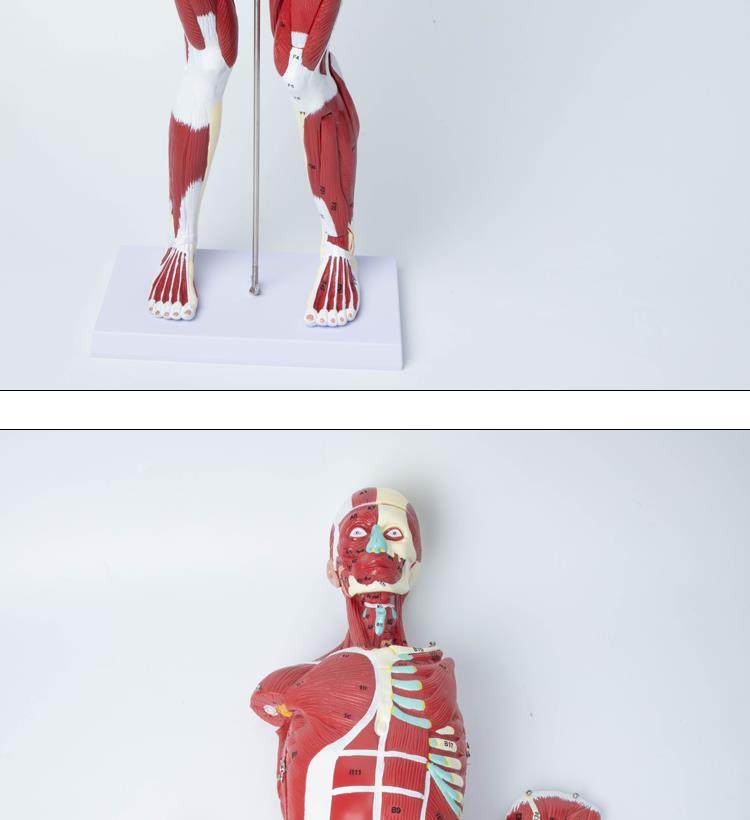

Human Body Muscle Internal Organ Disassembly Anatomy Structure Model Tissue Exercise Artificial Medical Teaching Aids

| Product Specifications | |

| Color Classification | 85 Human Muscle Internal Organs Removable Organ,50cm Muscle Model |